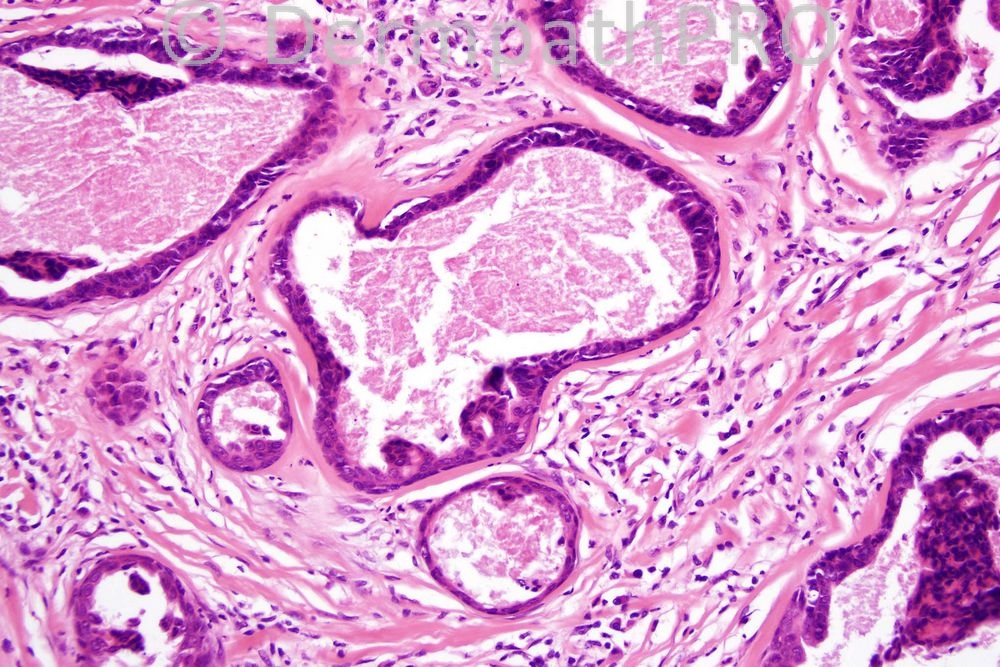

Female 30 years, nodule on arm.